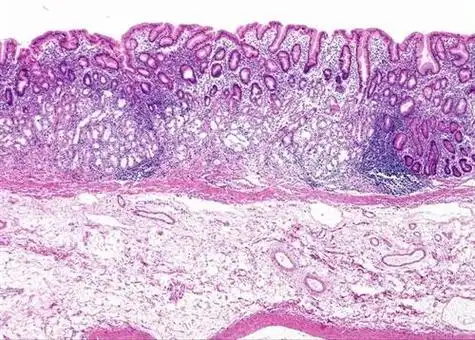

慢性萎缩性胃炎光镜

慢性萎缩性胃炎显微切片图片